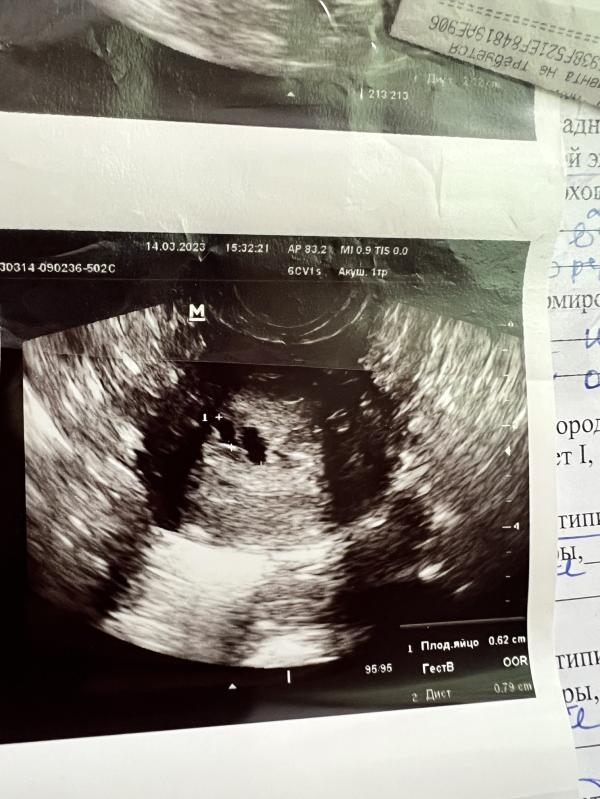

Ещё один сюрприз от бывшего. Детей я разумеется не планировала, то насморк которое он совершал надо мной я даже сексом назвать не могу. Я была уверена что всё впорядке. Месячные всегда регулярно и в срок. И в марте месячные начались и не закончились, разумеется я пошла к доктору, сделали узи, подозрение на замершую беременность с двумя плодами, отправили на чистку. Вчера пришла гистология которая подтвердила беременность. Сказать что я в шоке, ничего не сказать. Кто как восстанавливал здоровье после такого?